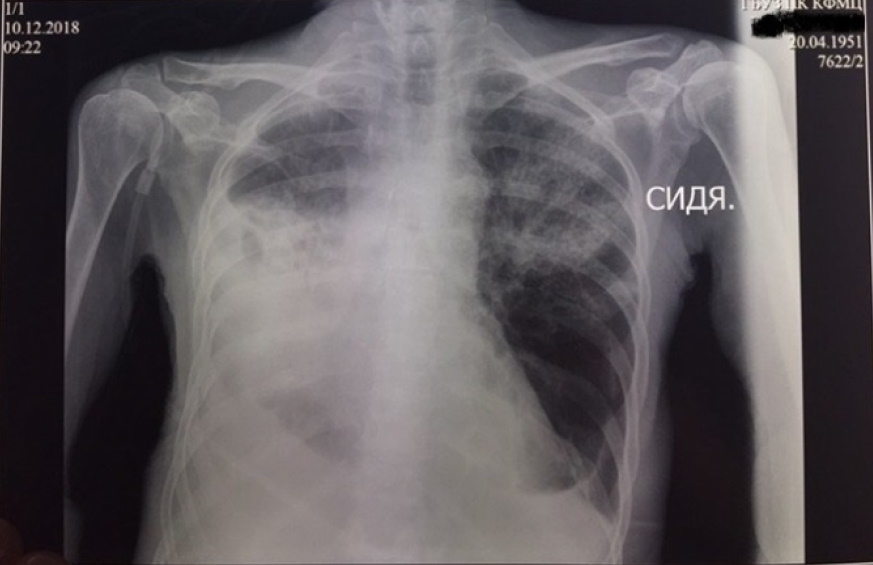

Рентгенография от 10.12.2018: в S1-2 левого легкого фокус инфильтрации, связанный с междолевой плеврой. В средних и нижних отделах правого легкого определяется обширная интенсивная инфильтрация, связанная с корнем и утолщенной плеврой. В правой плевральной полости определяется жидкость над диафрагмой. В левой плевральной полости незначительное количество жидкости (рис. 10).

Рис. 10. Рентгенограмма органов грудной клетки от 10.12.2018